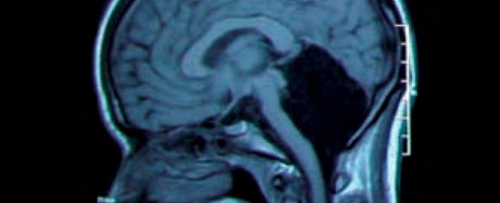

Năm 2007, các bác sĩ đã phát hiện ra trường hợp của một người đàn ông Pháp vẫn sống kỳ diệu mặc dù 90% não bộ đã tổn thương.

Vì cảm thấy chân trái của mình có vấn đề, người đàn ông 44 tuổi này đã đi đến bệnh viện khám. Chính lúc đó, ông đã được các bác sĩ thông báo về tình trạng tổn thương não nghiêm trọng của mình. Sau khi tiến hành chụp X-quang não, các bác sĩ đã vô cùng kinh ngạc khi thấy phần lớn não bộ của ông đã dần dần bị phá hủy trong suốt 30 năm qua bởi sự tích tụ của các chất lỏng trong não, tình trạng này được gọi là não úng thủy.

Mặc dù bị tổn thương tới 90% bộ não, một người đàn ông Pháp vẫn có thể sống và hoạt động bình thường, điều này đã thách thức sự hiểu biết của các nhà khoa học.

Mặc dù mô não chỉ còn lại một khoảng nhỏ, tinh thần và mọi hoạt động của người đàn ông này không bị ảnh hưởng. Chỉ số IQ của ông chỉ dừng ở con số 75 điểm, nhưng ông vẫn rất minh mẫn và luôn hoàn thành tốt công việc công chức của mình. Hiện tại ông đã kết hôn và có hai con, sức khỏe của ông tương đối khỏe mạnh.

Hiện nay, trường hợp của người đàn ông này khiến các nhà khoa học phải suy nghĩ lại về chức năng thực sự của bộ não. Liệu rằng bộ não của chúng ta có sử dụng hết 100% các khu vực, hay chỉ sử dụng 10%.